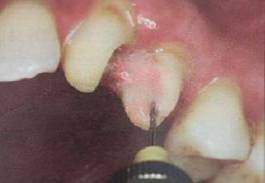

必要的情况下先开阔根管口建立一定的视角后,慢速手机上G钻为引导钻,由号递增引导开阔通路;P钻预备桩道,同样需要由小向大号递增,直到选择好适合的号预备到规定测量的深度即可,再配合纤维桩系统中各型号纤维桩所匹配的桩道钻,预备、修整成与纤维桩相适应的桩道。

预备后根管壁上会不同程度的牙胶和封闭剂等残留物,所以桩道预备前后建议X线片辅助检查预备深度等情况,而残留物也会很清晰地显现。